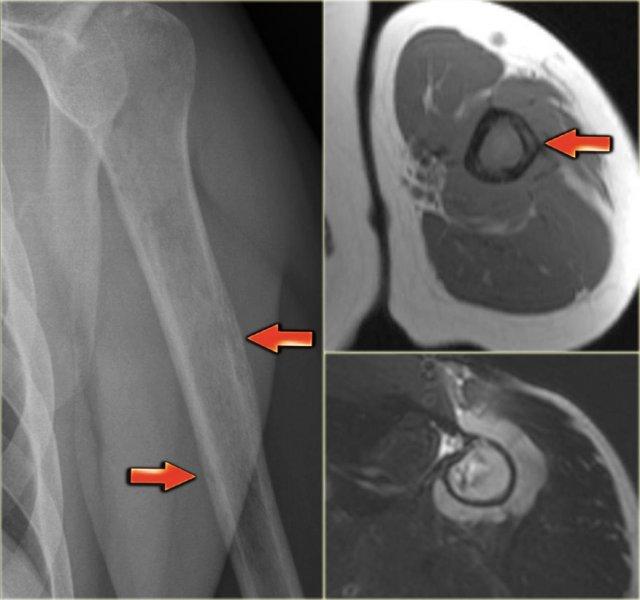

Ewing’s sarcoma in diaphysis of the femur. Notice ill-defined zone of transition (blue arrow) and aggressive type of periosteal reaction (red arrows)

Bên trái là hình ảnh bệnh nhân có u xương Ewing ở xương đùi.

Lưu ý vùng tiêu xương không rõ ranh giới.

Có phản ứng màng xương xâm lấn.

Phim X-quang thường bên trái cho thấy tổn thương tiêu xương không rõ ranh giới ở thân xương cánh tay.

Lưu ý hiện tượng xâm lấn dạng đường hầm qua vỏ xương (mũi tên đỏ).

Trên hình MR, lưu ý các bất thường dạng tuyến tính trong vỏ xương và khối mô mềm bao quanh theo chu vi.

Chẩn đoán phân biệt (tùy theo độ tuổi): Sarcoma Ewing, viêm tủy xương và u lympho xương.

Sinh thiết xác nhận u lympho không Hodgkin